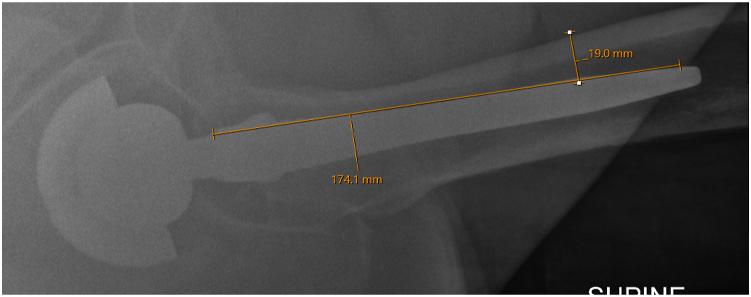

Osteotomy techniques used for wide exposure during femoral component revision include the extended trochanteric osteotomy and its modifications. We describe an anterior proximal femur osteotomy technique starting from the inside of the femoral canal at the bone-implant interface and heading outward. The technique is used in conjunction with the extended direct anterior approach and allows direct access to and visualization of the anterior, medial, and lateral bone-implant interfaces. This technique is most useful for the removal of collared, fully hydroxyapatite-coated double-tapered femoral stems, in which bone-implant interfaces need to be accessed for removal of a well-osseointegrated hip arthroplasty implant.

在股骨部件翻修术中用于广泛显露的截骨技术包括大转子延长截骨术及其改良术式。我们描述一种从股骨管内侧骨-植入物界面开始向外的股骨近端前侧截骨技术。该技术与直接前方延长入路联合使用,可直接显露并观察前方、内侧和外侧的骨-植入物界面。这项技术对于移除带颈领、全羟基磷灰石涂层的双锥度股骨干假体最为有用,在移除骨整合良好的髋关节置换植入物时需要显露骨-植入物界面。